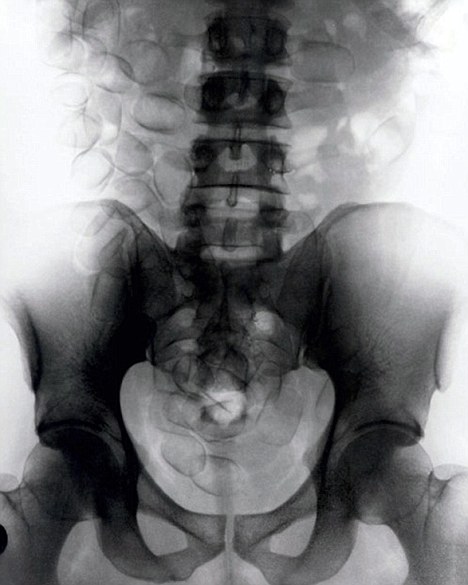

現(xiàn)年30歲的菲達利斯(Fidelis Ozouli)冒著生命危險將重達1公斤的毒品吞下,被抓后卻辯稱不知道吞下的是毒品。當(dāng)時,曼徹斯特機場的海關(guān)人員看到毒販菲達利斯臃腫的肚腩,顯得很不自然,于是開始懷疑。檢查人員用X射線機照他的胃部時,發(fā)現(xiàn)了大量可卡因。目前他已被送往附近醫(yī)院,以確保排出所有的毒品。